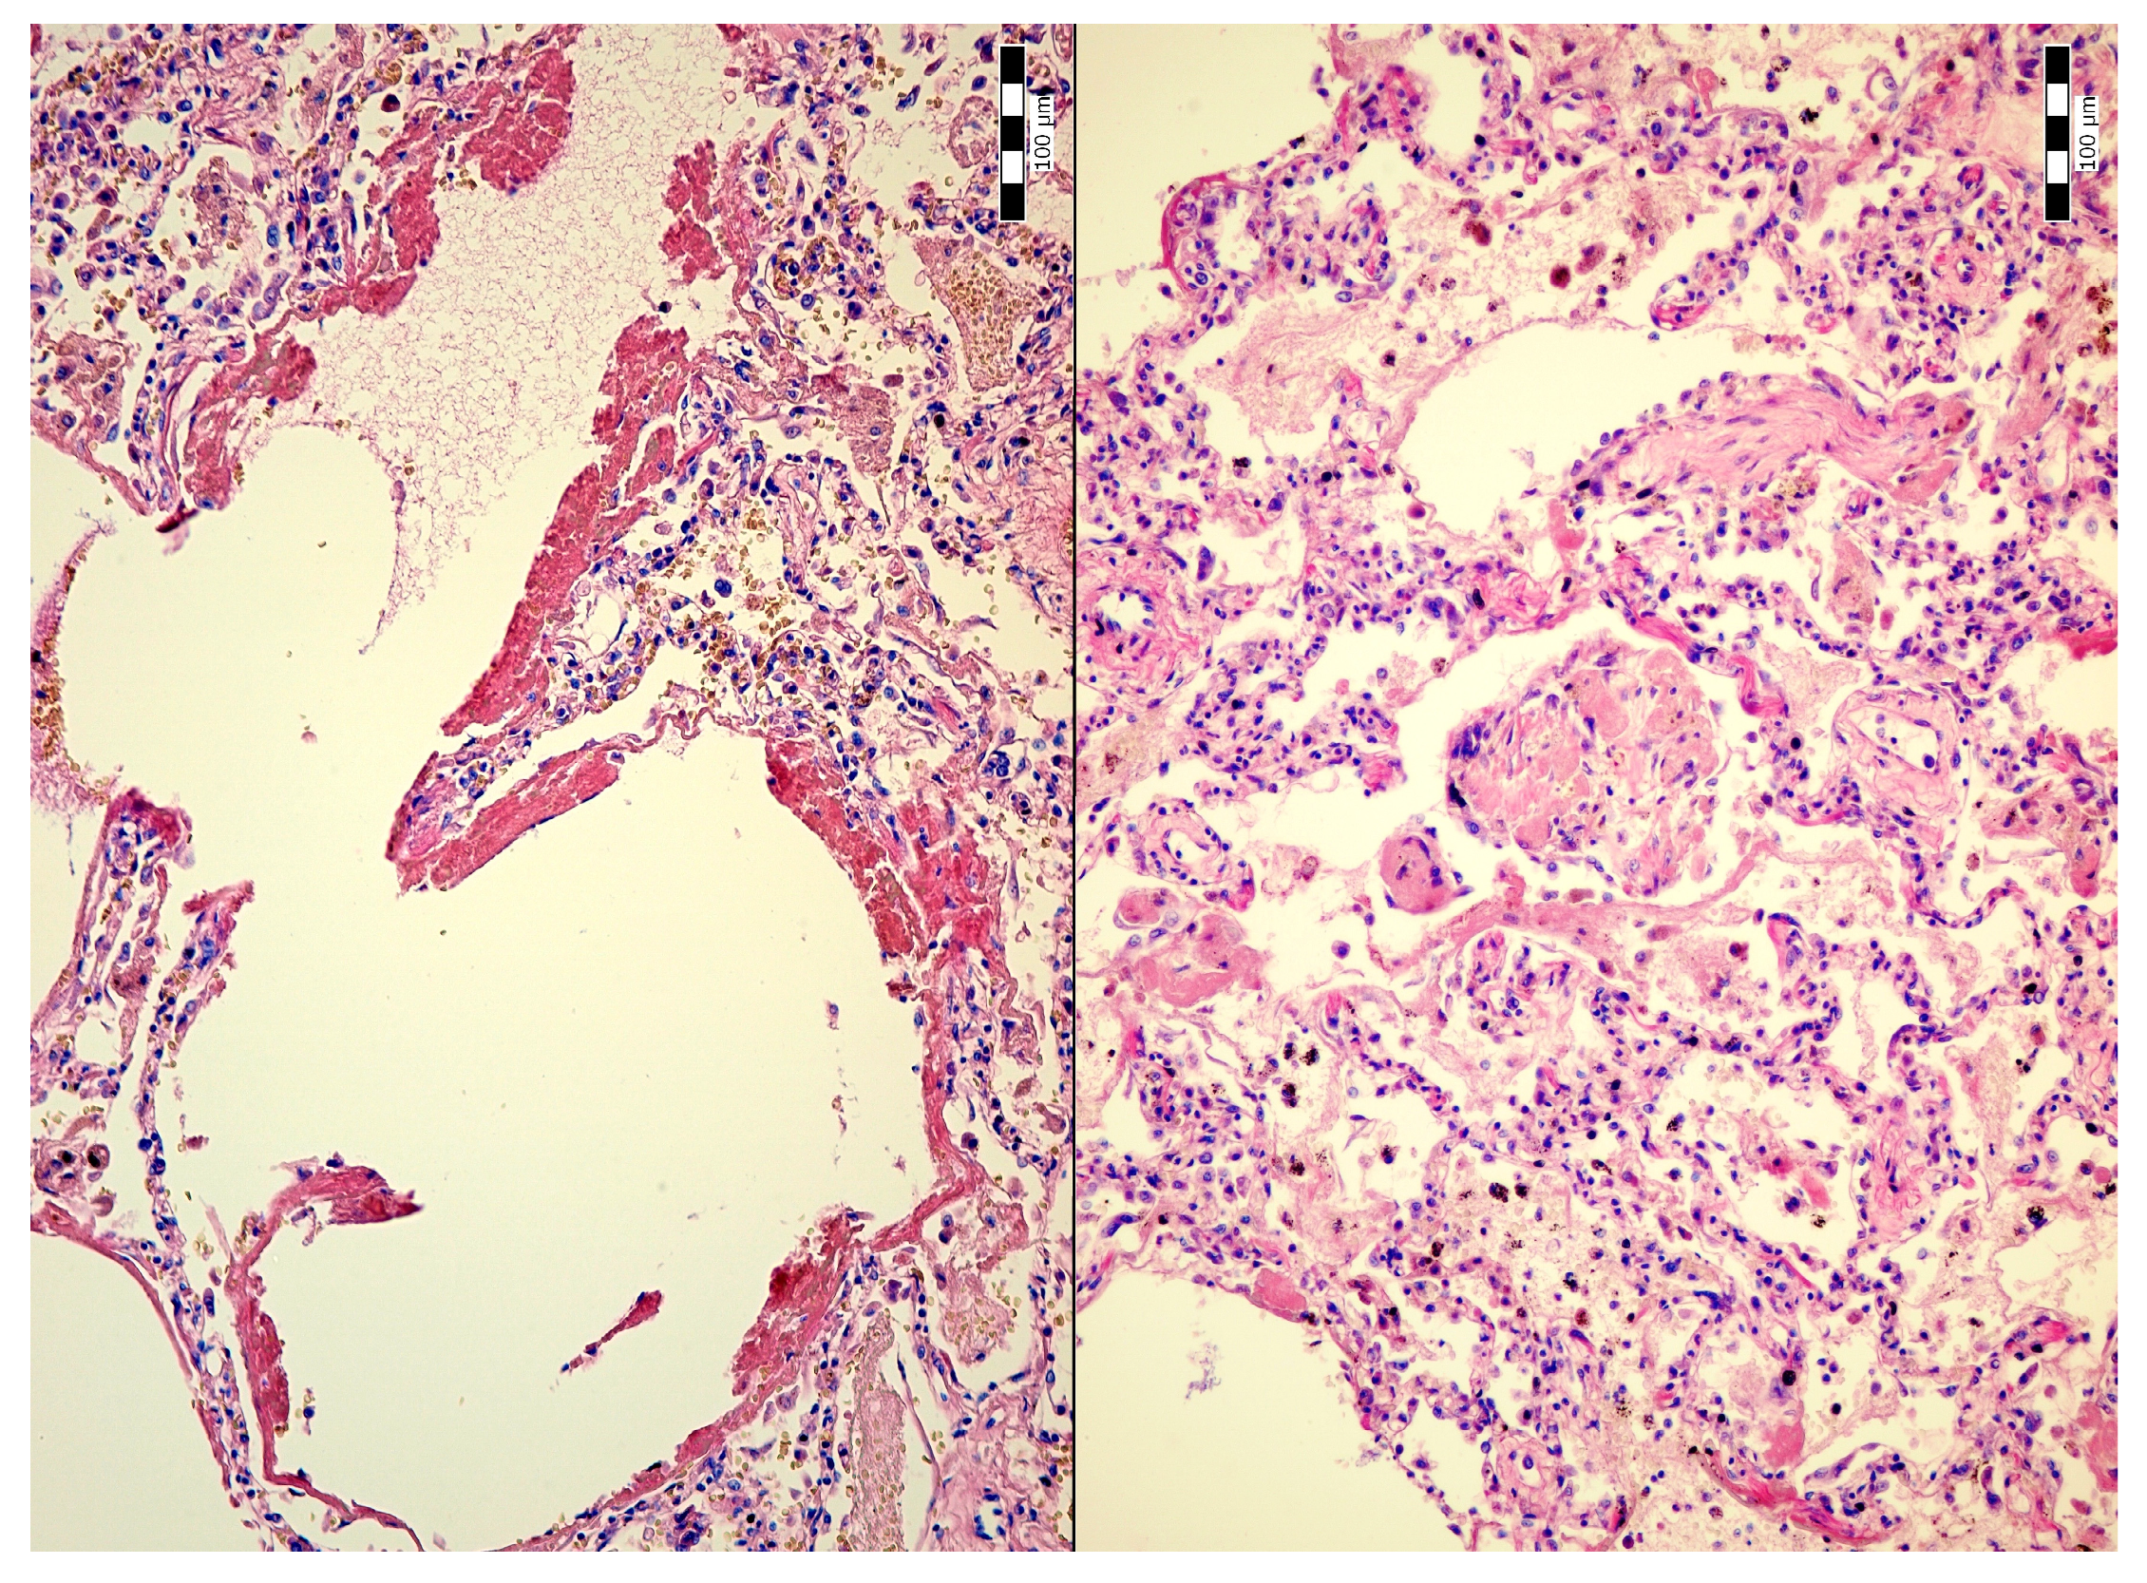

2. Case Description